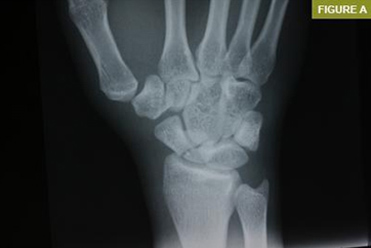

Skafoid kırıkları, diğer kemik kırıklarına göre daha zor teşhis edilir. Bunun nedeni, kırığın röntgende her zaman net bir şekilde görülememesidir. Bu nedenle, skafoid kırığı şüphesi durumunda MR veya BT gibi ileri görüntüleme yöntemlerine başvurulabilir.

Skafoid Kırığı Röntgen ve Teşhis

Skafoid kırıklarının teşhisi için röntgen en sık kullanılan yöntemdir. Ancak, bazı durumlarda röntgen kırığı göstermeyebilir. Bu nedenle, MR veya BT gibi ileri görüntüleme yöntemlerine başvurulabilir.